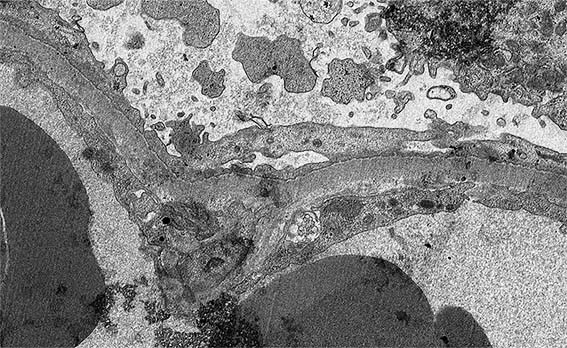

Figure 8. EM, original magnification x 4,500. Detail the podocyte cytoplasm.